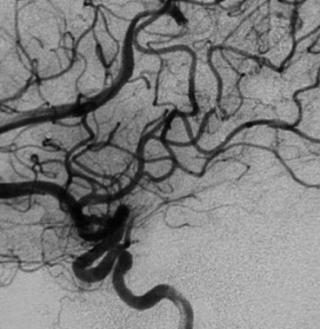

- Форма сосуда устанавливается по наличию сужений, деформаций или аневризматических изменений, что имеет значение для диагностики степени поражения.

Высокая – определяет участки сужения, окклюзии и аневризмы |